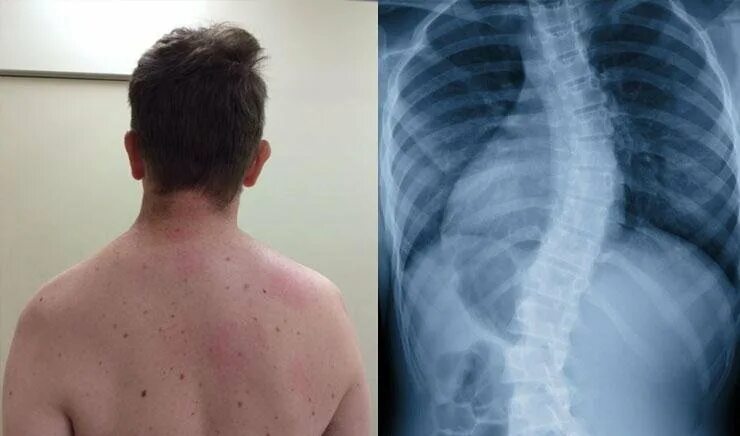

Идиопатический грудопоясничный сколиоз. Рентгенография позвоночника сколиоз. Сколиоз позвоночника 2 степени. S образный грудопоясничный сколиоз 2 степени. Сколиоз 2 степени рентген.

Сколиоз позвоночника 3 степени рентген. Кифоз сколиоз 4 степени. 1 стадия склероза. Сколиотическая деформация грудной клетки. Склероз 3 степени.

Сколиотическая деформация позвоночника 40 градусов. Сколиоз грудного отдела 4 степени. Склероз 3 степени. Сколиоз 3 степени рентген. Склероз 3 степени.